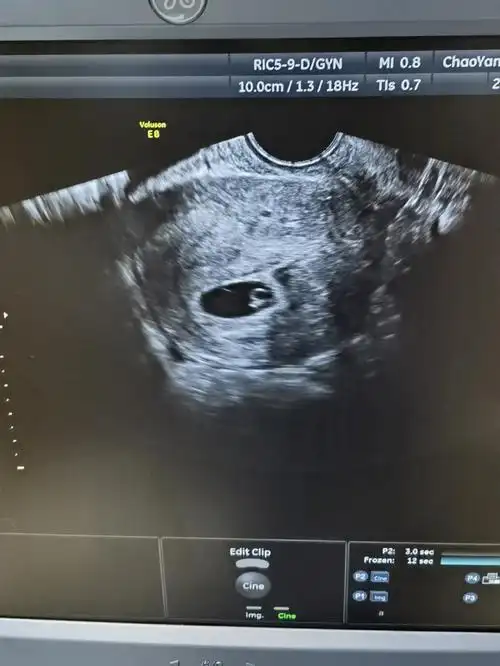

终于接到了属于我的热乎乎的胎芽胎心